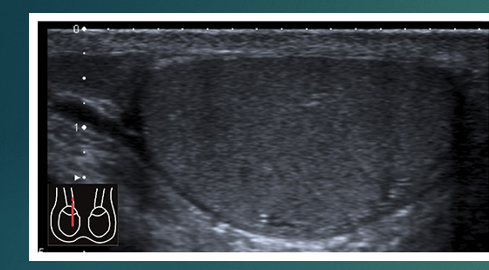

List caudal, cranial, anterior and posterior

list the 2 pieces of anatomy

what do you see